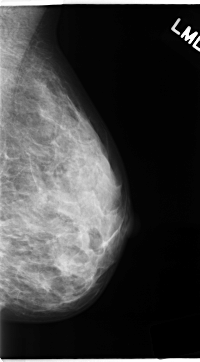

C_0139_1.LEFT_MLO

LEFT_MLO LINES 4696 PIXELS_PER_LINE 2592 BITS_PER_PIXEL 12 RESOLUTION 50 NON_OVERLAY